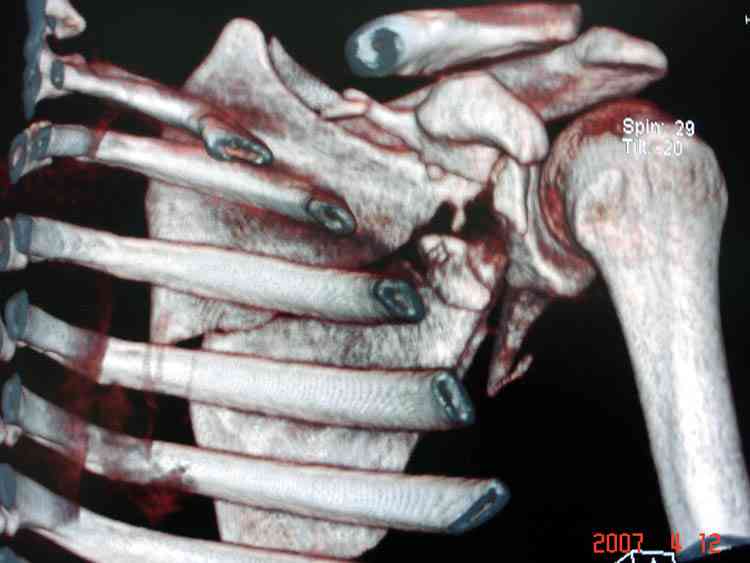

На снимке (№6 компьютерная томограмма и 3D №7) перелом клювовидного отростка.

Передним дельтопекторальным Bankart доступом намного легче провести фиксация отростка, но тогда репозиция и фиксация колонн затрудняется, поэтому был применен стандартный Judet задний доступ.

Репозицию смогли сделать пальцами через щель между

шейкой и телом лопатки (последний 3D снимок)

Двумя шурупами сзади на пластине (вместе шайбы)

провели удержание репозиции, а фиксацию провели

следующим косым шурупом.

Последующие этапы на снимках.